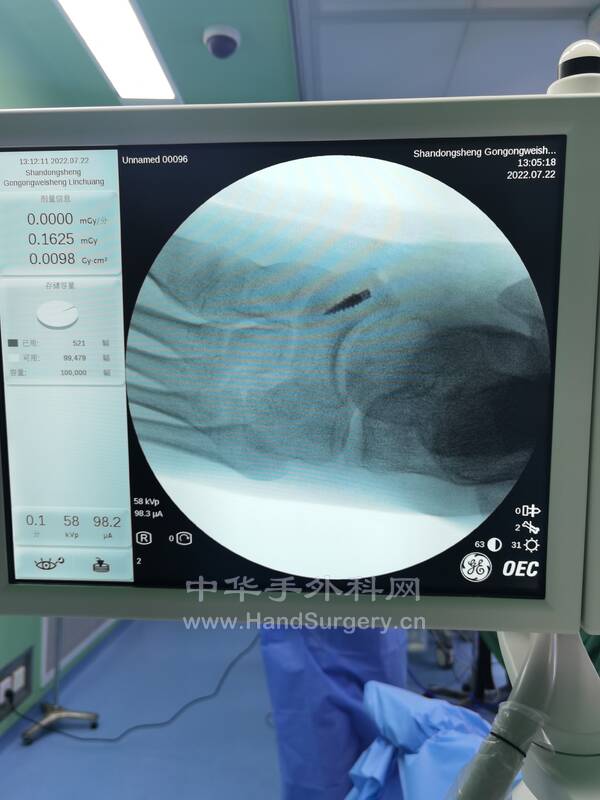

2.马蹄内翻足矫正术:

术式:跟腱延长术,跖筋膜松解术,胫前肌腱部分转位术(术中发现第三腓骨肌过细,(见图),以5.0mm铆钉固定于楔骨,编织固定胫前肌腱),跟骨截骨外移内固定术,第一跖骨上抬固定术,环形外固定架固定术